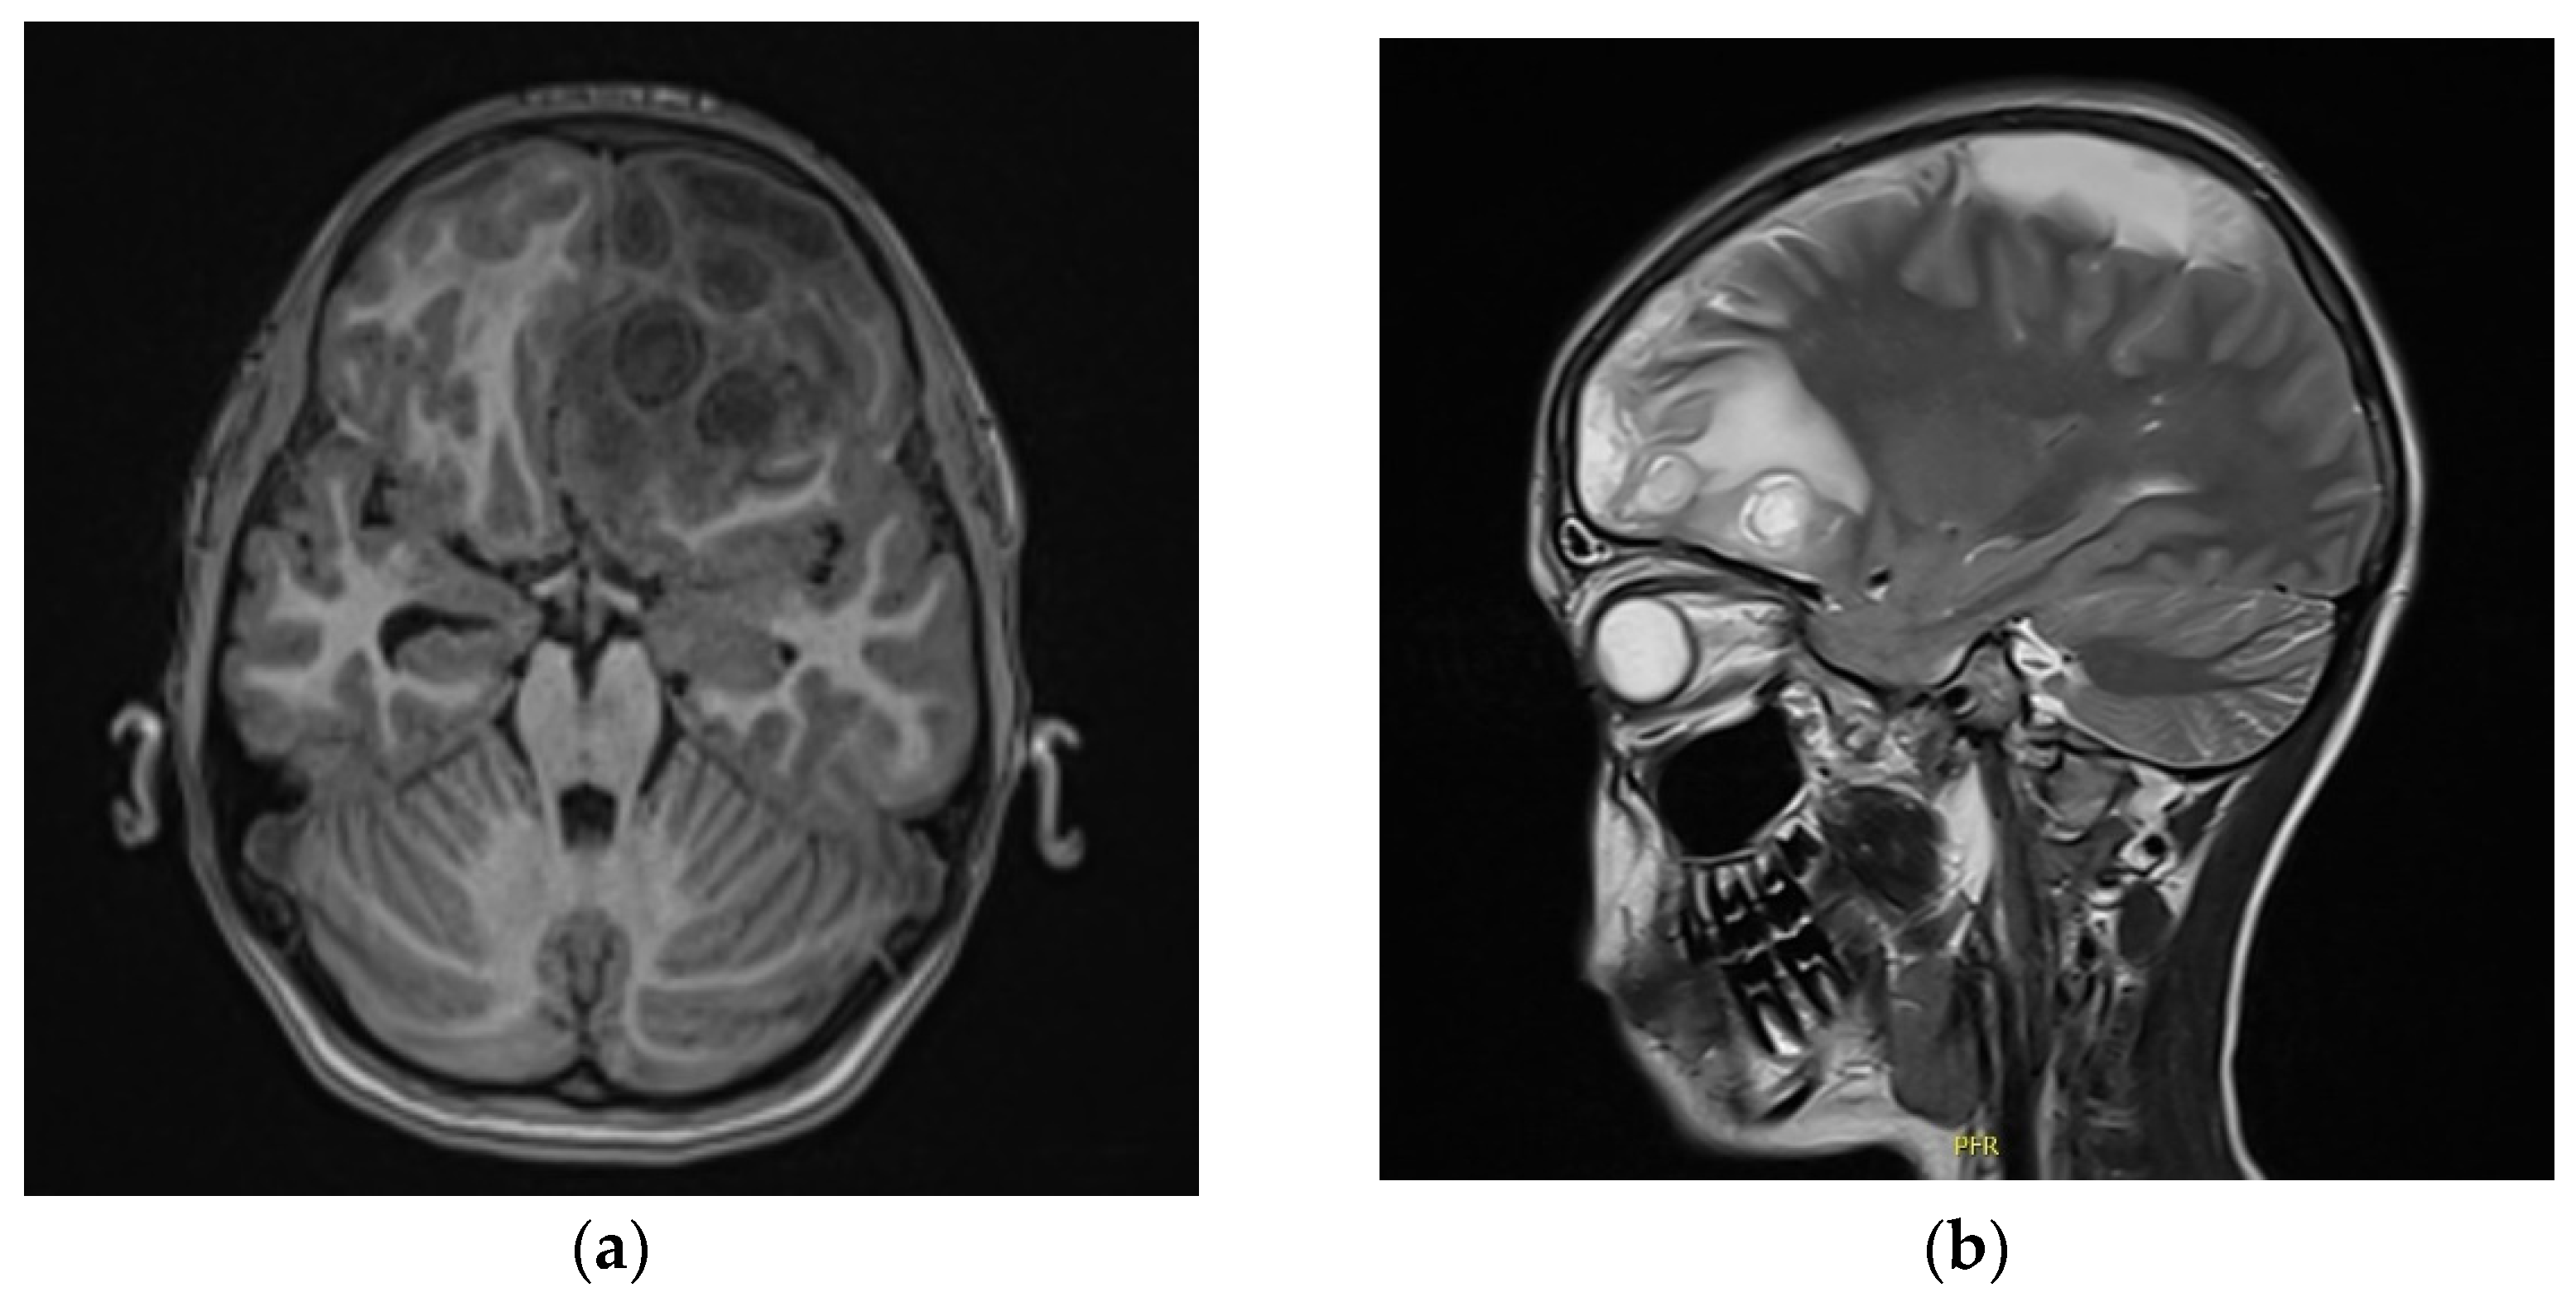

2. Case Report

3.2. Brain Abscesses